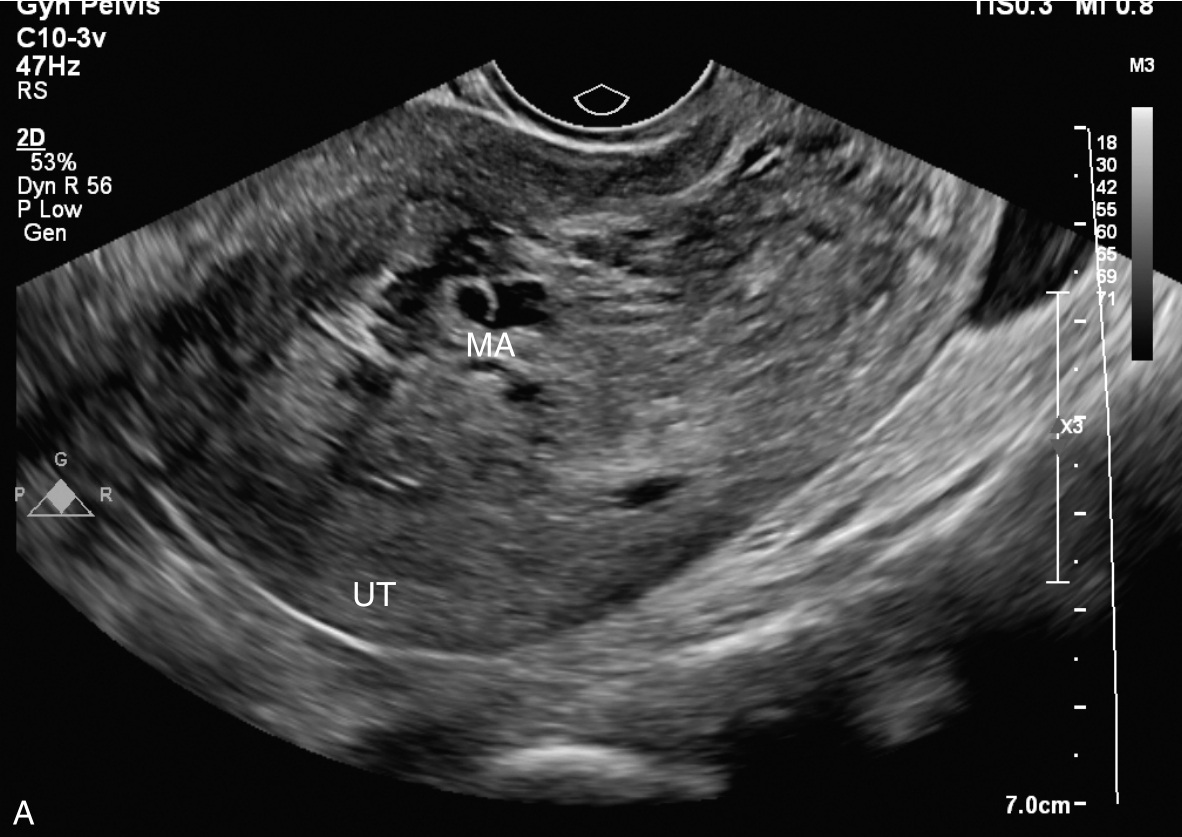

经阴道超声检查见图3-10-1。子宫前位,宫体大小5.6cm×6.9cm×6.5cm,宫腔内查见7.1cm×2.6cm×3.5cm不均质稍强回声,其内回声极不均匀,其内可见多个无回声区,最大无回声区的最大径为0.8cm,周边及其内探及丰富血流信号,该团块与子宫前壁关系密切。宫颈后唇查见囊性占位,大小为2.5cm×1.3cm×1.9cm,囊液清亮,未探及明显血流信号。双附件区未见确切占位。超声检查结果:宫腔内占位,宫颈后唇囊性占位。

图3-10-1 常规超声声像图

A.子宫矢状切面显示宫腔内稍强回声;B.子宫横断面显示宫腔内强回声;C.子宫矢状切面显示宫颈管内占位;D.宫颈管内占位的血流情况;E.宫腔占位的血流情况;F.宫颈囊性占位(箭头所示)。UT:子宫;C:宫颈;MA:肿物。